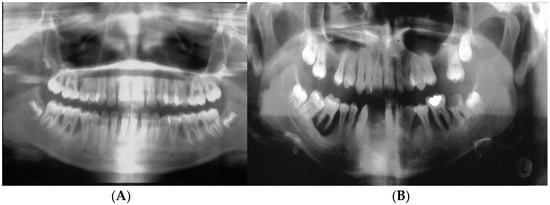

6. Distinct Characteristics of LAgP and an Alternative Approach for Assessing Treatment Success

- (A)

- Distinct Characteristics of LAgP: An Illustrative Case.

- Another way of Assessing Periodontitis Treatment Success.